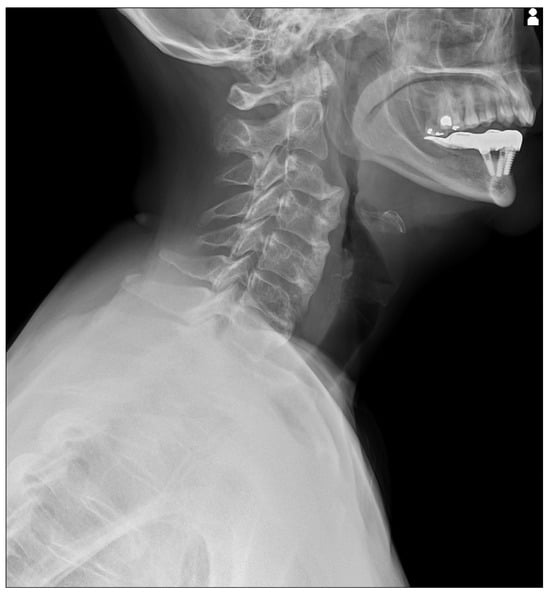

Figure 1. Static X-Ray acquisition acquired with Konica Minolta (AeroDR TX, Konica Minolta Inc., Tokyo, Japan) with a static setting. The cervical X-Ray shows florid, flowing ossification along the anterior or right aspects of five contiguous vertebrae, from C3 to C7 [,,,,,]. The intervertebral disk spaces are preserved.